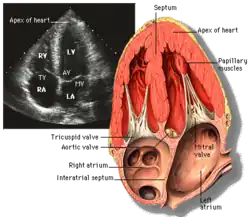

Echocardiography

Echocardiography is regularly utilized to diagnose, manage, and monitor patients with suspected or established heart ailments, making it a highly prevalent diagnostic imaging technique in cardiology due to its speed and efficiency.[3]

Transthoracic echocardiography (TTE) uses ultrasonic waves for continuous heart chamber and blood movement visualization. It is the most commonly used imaging tool for diagnosing heart problems, as it allows non-invasive visualization of the heart and the blood flow through the heart, using a technique known as Doppler.